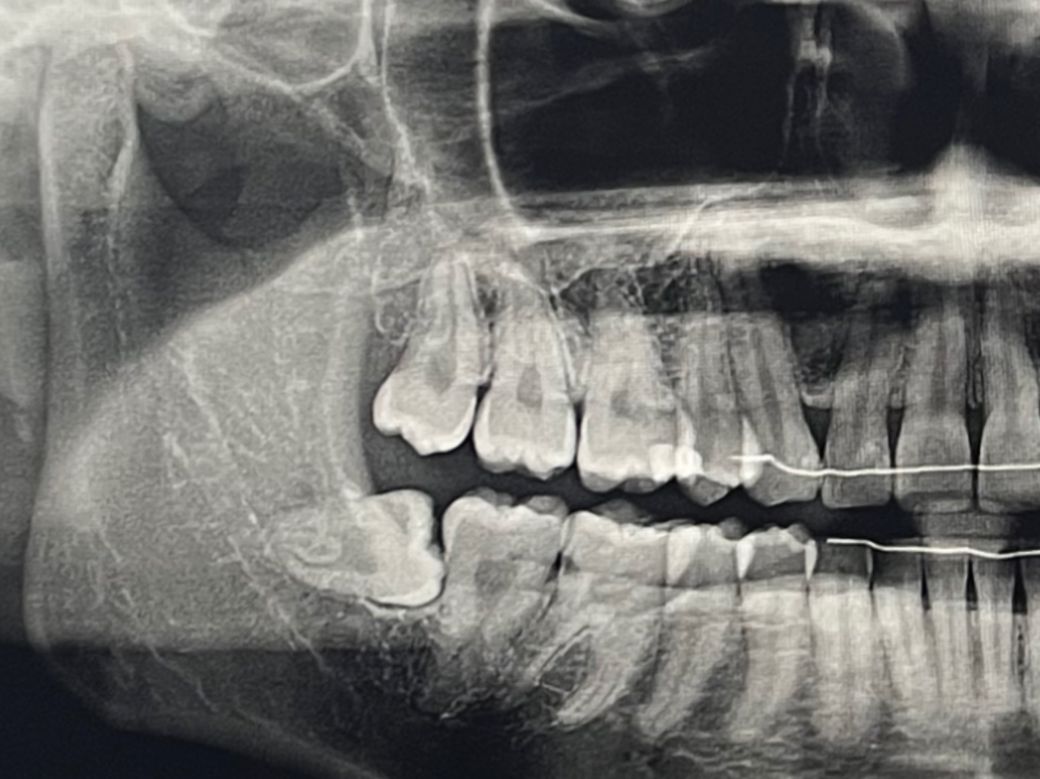

사진상 왼쪽 아래 ( 실제로는 오른쪽입니다) 아래 매복니에 음식물이 너무 많이 끼고 아파서 무조건 뽑을 예정입니다. 근데 혹시 그 위 사랑니도 (매복 아니고 똑바로 잘 났습니다) 같이 뽑아야할까요? 같이 뽑는 게 좋을까요??

이게 그 옆 어금니랑 같이 저작기능을 할 수 도 있어서 안 뽑는 게 좋을지 궁금합니다..! 사진상에서는 어금니랑 사랑니랑 교합하지 않는 것처럼 보이지만 저게 단면 파노라마 사진이라.. 궁금합니다

• 1번 째 사진